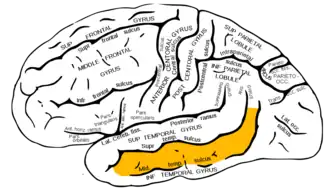

Lateral surface of left cerebral hemisphere, viewed from the side. (Middle temporal gyrus shown in orange.) | |